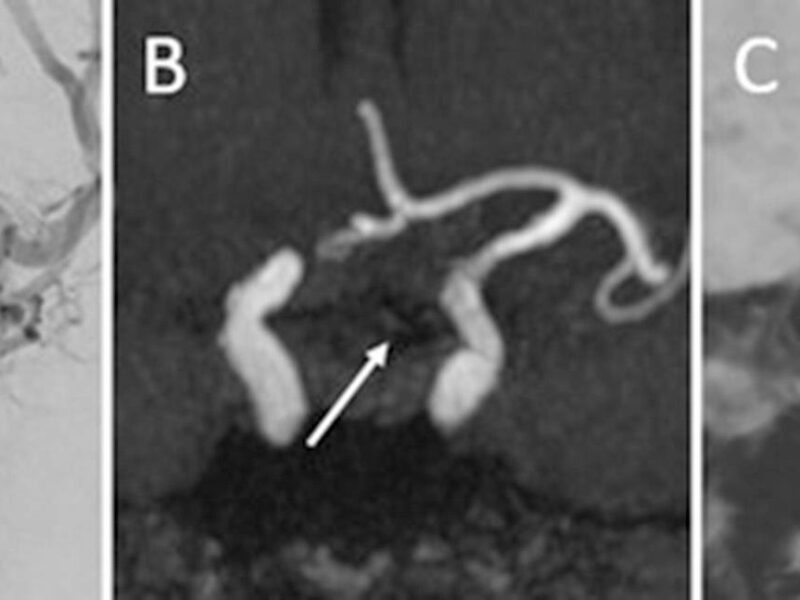

Des dispositifs d'hypnose par réalité virtuelle permettent d'accompagner les patients en radiologie interventionnelle. Grâce à une stimulation visuelle et auditive, ils sont déconnectés de l'environnement hospitalier et ressentent moins le stress et la douleur.

Les casques de réalité virtuelle proposent aux patients de se plonger dans des ambiances relaxantes et de mieux supporter la douleur et l'anxiété lors des procédures interventionnelles. © Greg Matter/HypnoVR